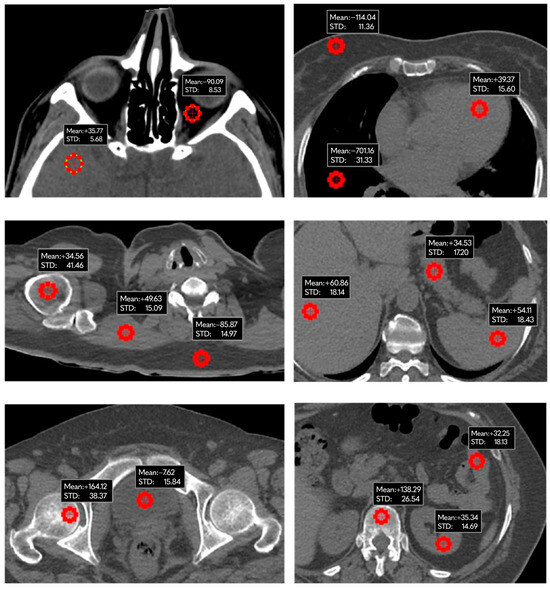

2.4. Data Collection and Analysis